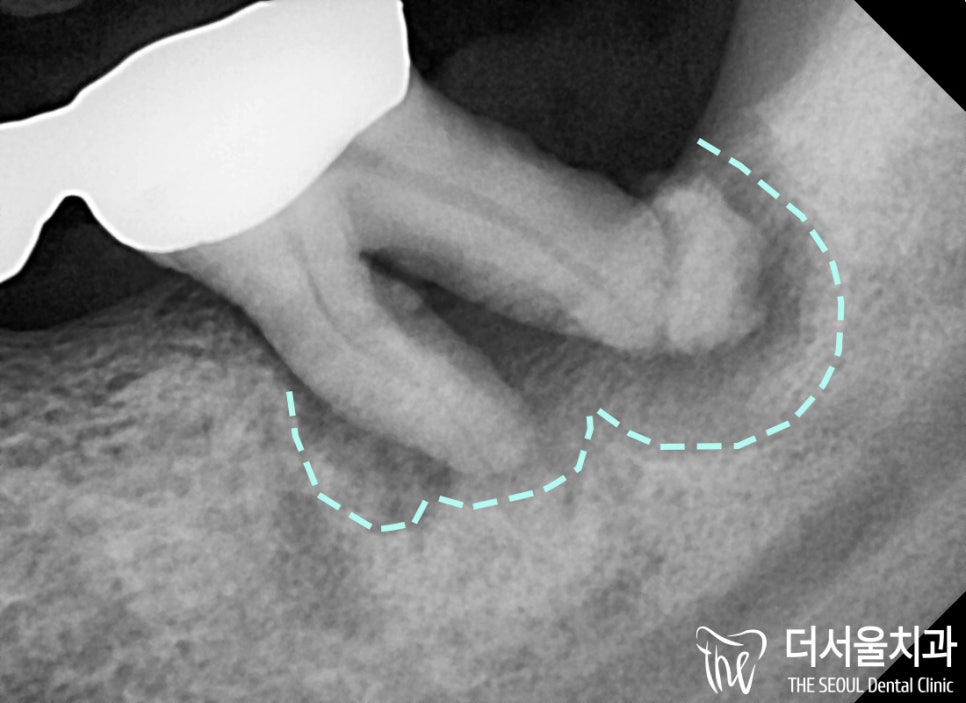

확대된 사진으로 보면

‘더욱’ 명확하게 확인해 볼 수 있었습니다.

뿌리 끝 염증과 심한 치주염으로

인공치인 Pontic과 함께 제거하게 되었습니다.